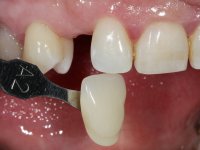

Female patient, 43 years old, non-smoker. Showed an edentulous space in the upper right canine area, resulting from tooth 1.3 impaction. The space had a mesio-distal diameter reduced to the normal size of the upper canine. This is consistent with the presence in the arch of the deciduous canine up to two years ago). Orthopantomography allows clearly view of tooth 1.3 impaction.The patient has a thick gingival phenotype and tolerable oral hygiene.

To define the dental zone to be covered by the Maryland bridge retainers, the patient was asked to perform maximum intercuspidation movements, and the contact points were marked with articular paper. Tooth preparation of the interproximal surfaces was made, to create a prosthetic insertion axis. It was sought that the mesio-distal diameter at the incisal level was equal to the diameter mesio-distal at the cervical level, that is to say, the interproximal walls were parallelized. Tooth preparation was done with fine grain diamond drills, and later polishing was done with abrasive discs. Color information was collected even before confection of the impression, to avoid dehydration of the arcade. Definitive impression was made using wash technique impression with silicone of heavy and regular consistency, both with fast setting, and a working plaster model was prepared in the lab. A laboratory scanner was used to scan the working model, and later, the infrastructure for the Maryland bridge was made using a CAD-CAM process. Ceramic was placed on this subframe. A ceramic adhesive was applied to the internal surface of the wings and connectors, which would enable bonding to the adjacent teeth. The adhesive bridge was bonded in the mouth following the conventional bonding technique. After bonding, the protrusion and laterality movements were carefully checked to avoid undesirable contacts.